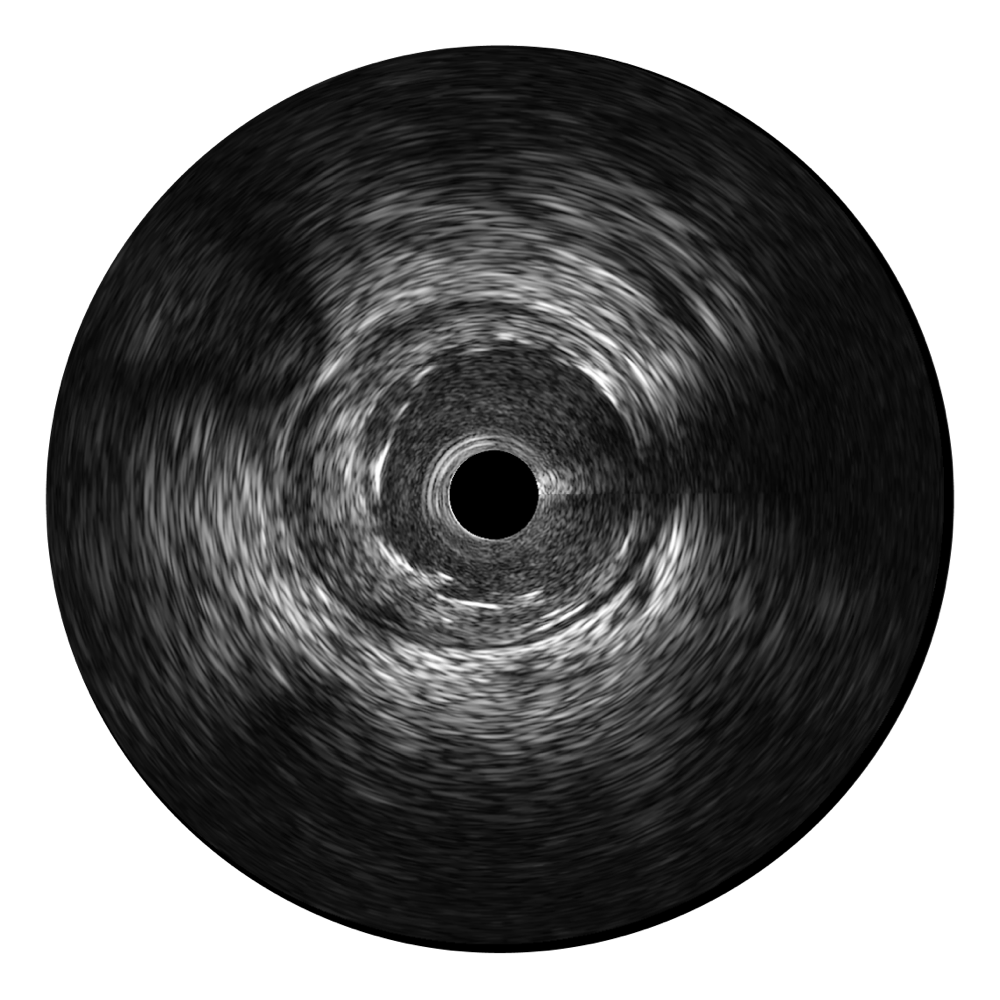

MILE米乐集团官网宽频IVUS图像

对比传统IVUS导管成像,MILE米乐集团官网宽频IVUS图像的近场支架梁显影更细腻,远场中膜外血管仍清晰可辨,兼顾远中近,兼顾分辨力与穿透深度